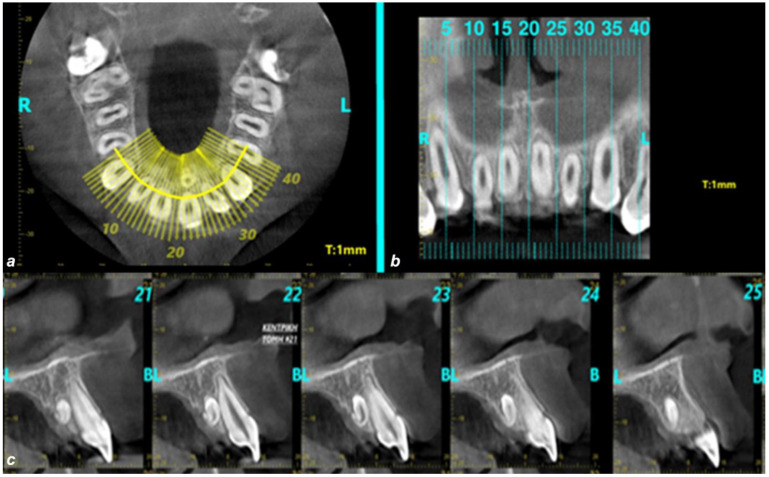

背景/目的:本回顾性研究的目的是调查非综合征希腊儿童和青少年上颌前区多生牙,以及它们与人口统计学特征和影像学表现的可能相关性。方法:研究样本包括224名年龄在18岁以下的儿童和青少年的锥形束计算机断层扫描(CBCT)。研究了上颌前区多生牙的位置、形态、与邻近解剖结构和邻近牙齿的关系以及可能的意义。结果:224例患者中有26例(11.6%)出现多牙。男性的患病率高于女性(分别为61.5%和38.5%)。在26名被诊断为多牙的儿童/青少年中,80.8%的儿童/青少年有一颗多牙,19.2%的儿童/青少年有两颗多牙。绝大多数多生牙阻生(92.3%),57.7%多生牙形态为锥形。正常体位占38.5%,倒置体位占26.9%,水平体位占19.2%,其他15.4%。84.6%的病例定位于腭部,50%的病例定位于中线。结论:希腊儿童和青少年多生牙的发生率为11.6%,多生牙多呈单牙、阻生、锥形、牙向正常。然而,由于抽样策略的局限性和本研究的有限推广性,这些结果应该谨慎解释。强调需要进一步研究,以加强对不同人口的更广泛适用性。这些发现有助于更全面地了解多生牙齿的患病率,有助于制定更准确和个性化的儿童和青少年牙科治疗计划。这将有助于避免病人的牙齿将来出现问题。

Background/Objectives: The aim of this retrospective study was to investigate the supernumerary teeth located in the anterior region of the maxilla of non-syndromic Greek children and adolescents, as well as their possible correlation with demographic characteristics and radiographic findings. Methods: The study sample comprised cone-beam computed tomography (CBCT) scans from 224 children and adolescents aged up to 18 years. The following parameters were studied: location of supernumerary teeth in the anterior maxillary area, their morphology, their relationship to adjacent anatomical structures and adjacent teeth, and potential implications. Results: Out of the 224 cases 26 (11.6%) presented supernumerary teeth. There was higher prevalence in males than females (61.5% versus 38.5%, respectively). Among the 26 participants diagnosed with supernumerary teeth, one supernumerary tooth was found in 80.8% of children/adolescents, while 19.2% had two supernumerary teeth. The vast majority of supernumerary teeth were impacted (92.3%), and their morphology in 57.7% of cases was conical. A total of 38.5% of cases had normal orientation, 26.9% inverted orientation, 19.2% horizontal orientation, and 15.4% other. The localization was palatal in 84.6%, and the area of localization for 50% of cases was the midline. Conclusions: The prevalence of supernumerary teeth in the studied sample of Greek children and adolescents was 11.6% and tended to appear as single, impacted, conical, and with normal orientation. However, these results should be interpreted with caution, due to the limitations in the sampling strategy and the restricted generalizability of this study. The need for further research to enhance broader applicability for different populations is highlighted. These findings are instrumental for a more comprehensive understanding of the prevalence of supernumerary teeth, contributing to more accurate and individualized dental treatment planning in children and adolescents. This will help to avoid future issues in the patient's dentition.